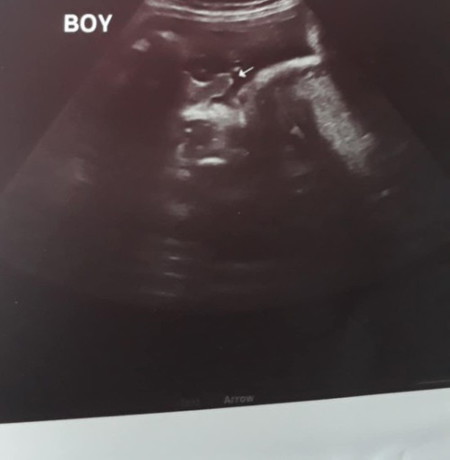

Hello po ! 35 weeks sa Pelvic Ultrasound. Boy po ba talaga? Salamat po sa sasagot.

yes po it's a boy, ganyan na ganyan din baby boy ko nung ultrasound nya

Yes po it’s a boy, turtle shape po kasi hehe congratulations po

Nakatayo na ang totoy niya. Ganyan din sa unang ultrasound ko e

yes po boy kitang kita po 😊